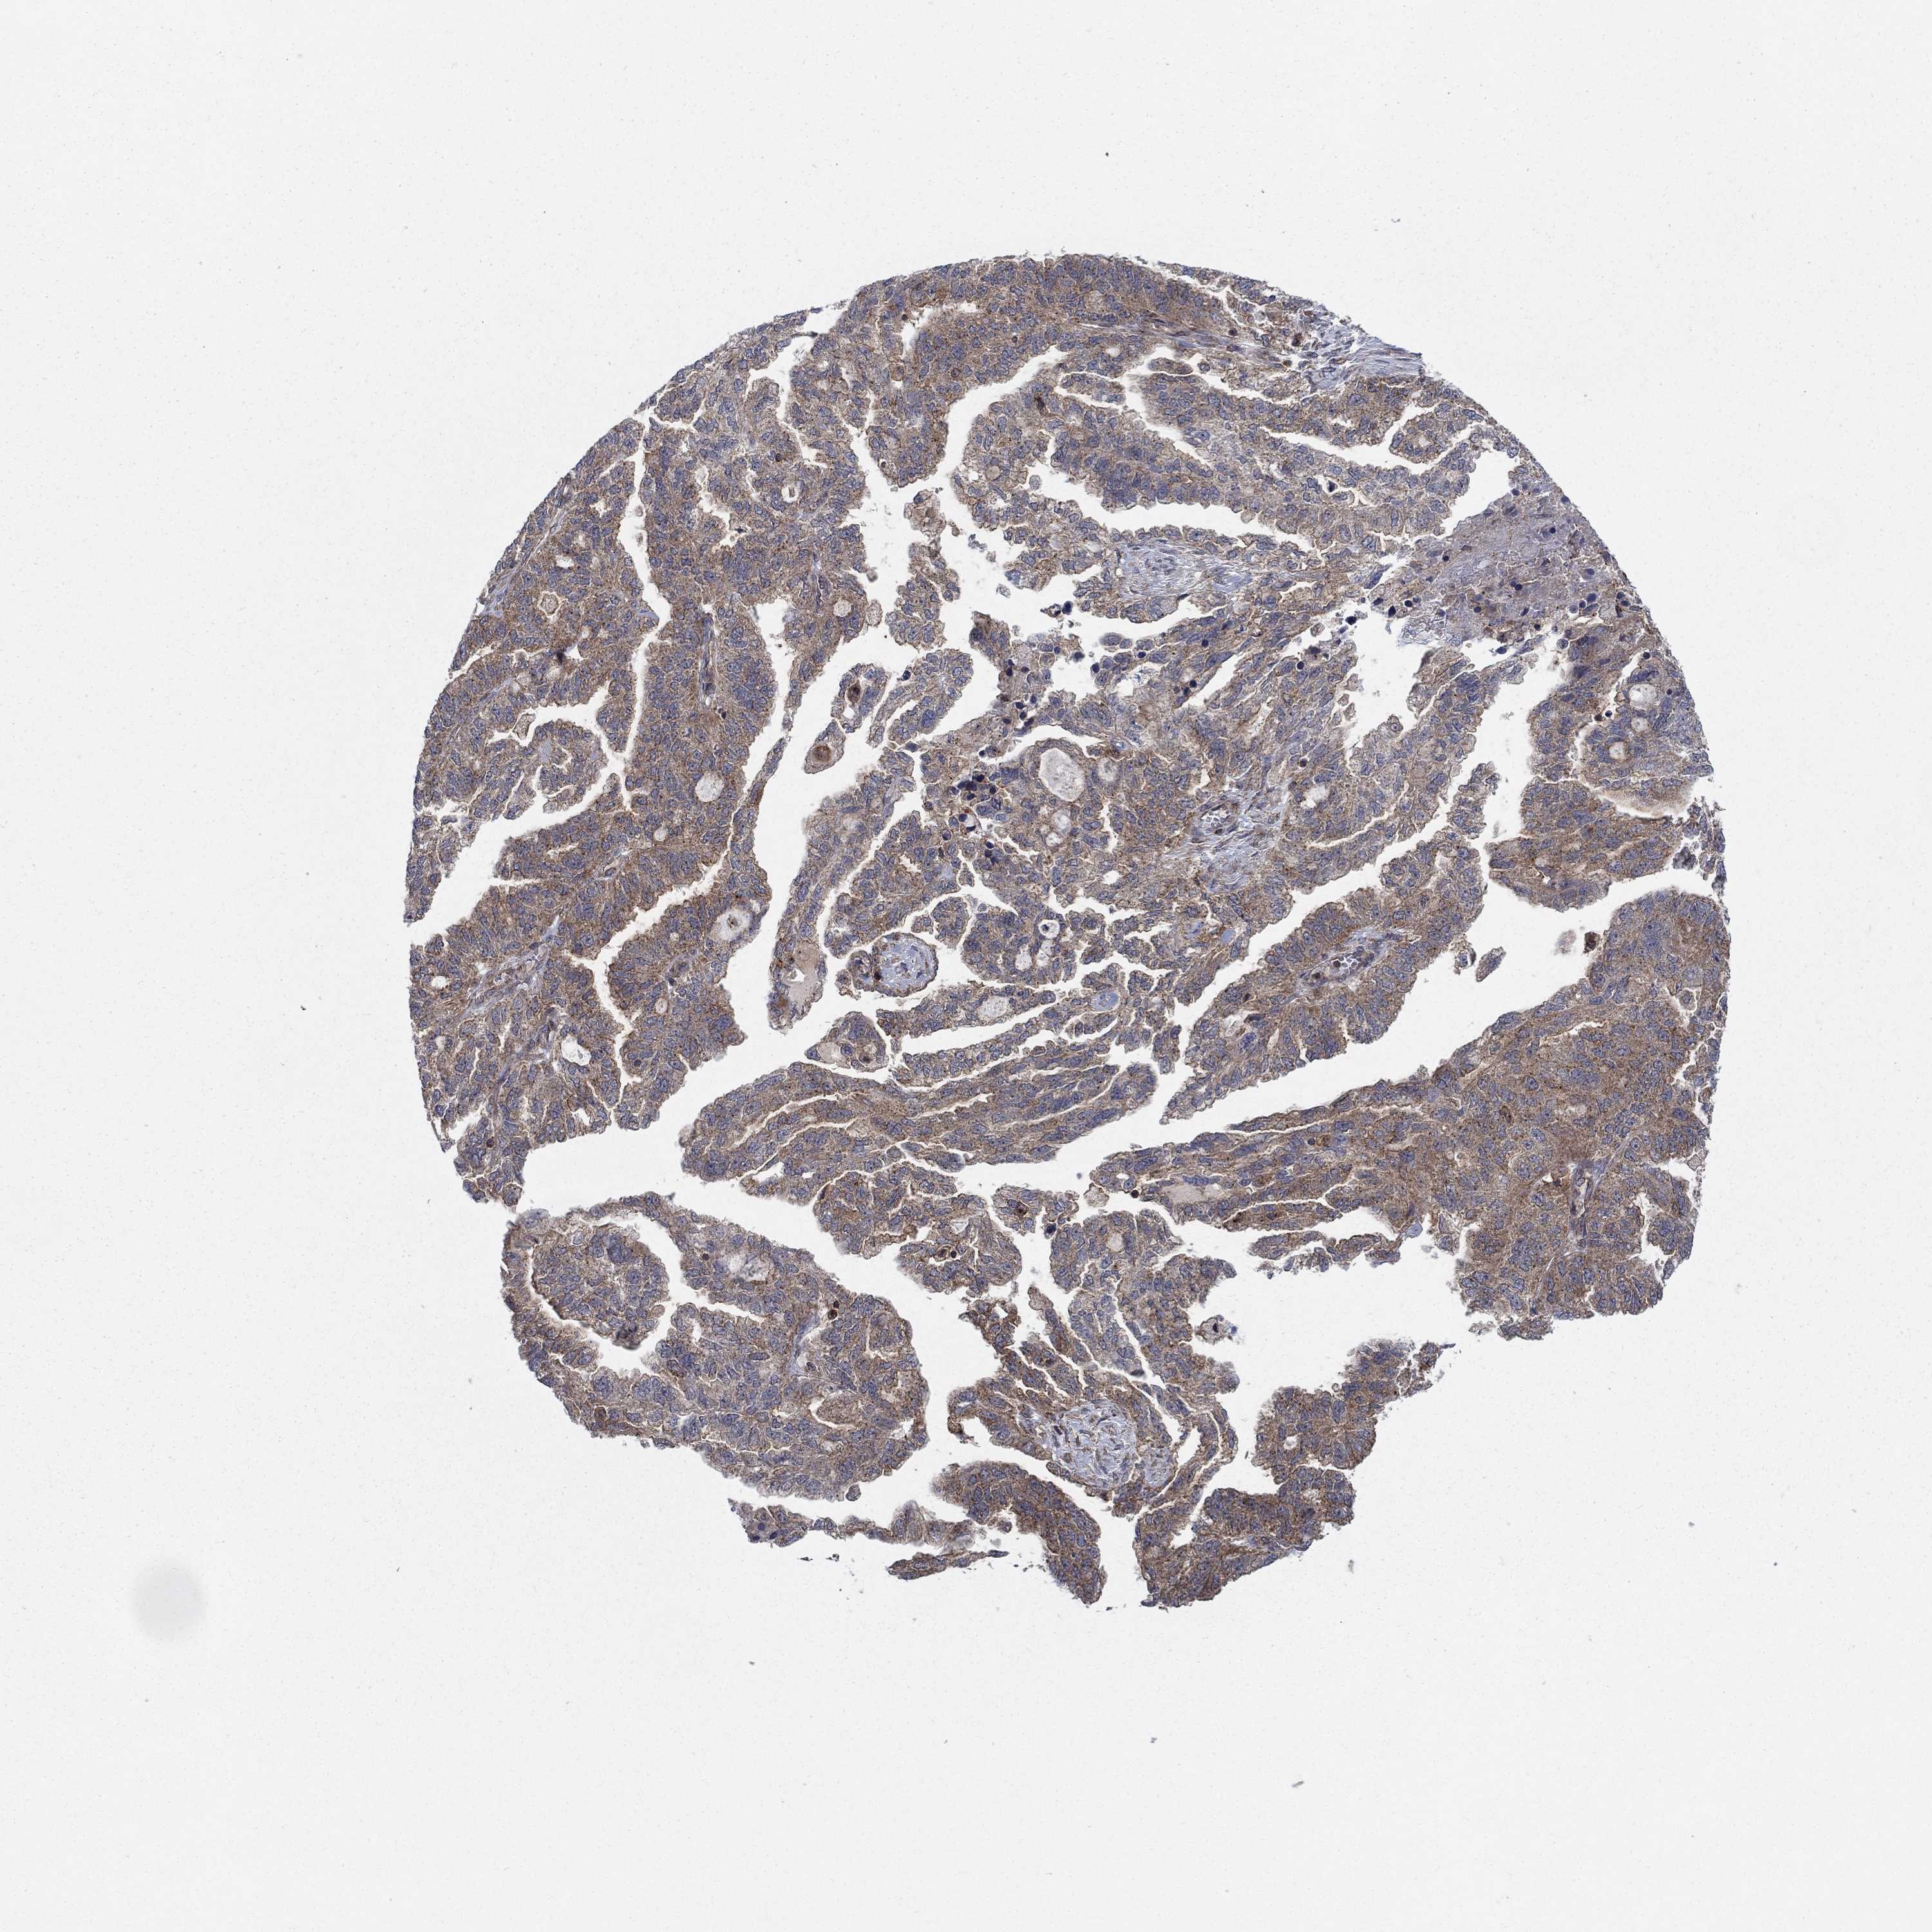

OVARIAN CANCER - Protein expressioni

A mouse-over function shows sample information and annotation data. Click on an image to view it in a full screen mode. Samples can be filtered based on level of antibody staining by selecting one or several of the following categories: high, medium, low and not detected. The assay and annotation is described here.

Note that samples used for immunohistochemistry by the Human Protein Atlas do not correspond to samples in the TCGA dataset.

Antibody stainingi

Antibody staining in the annotated cell types in the current human tissue is reported as not detected, low, medium, or high, based on conventional immunohistochemistry profiling in selected tissues. This score is based on the combination of the staining intensity and fraction of stained cells.

Each image is clickable and will lead to virtual microscopy that enables deeper exploration of all samples and also displays staining intensity scores, fraction scores and subcellular localization as well as patient and tissue information for each sample.

Antibody HPA075580

Staining

High

Medium

Low

Not detected

Intensity

Strong

Moderate

Weak

Negative

Quantity

>75%

75%-25%

<25%

None

Location

Nuclear

Cytoplasmic/membranous

Cytoplasmic/membranous,nuclear

Cystadenocarcinoma, serous, NOS

Cystadenocarcinoma, mucinous, NOS

Carcinoma, endometroid